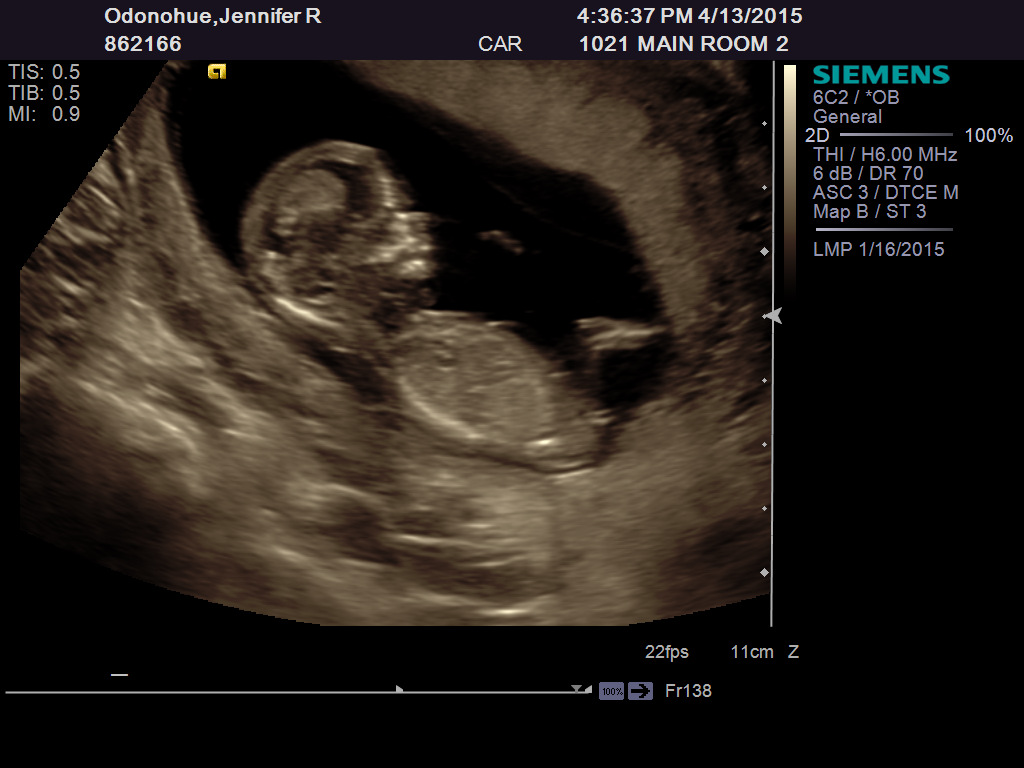

Leaning boy, looks like the nub is on the rise.

Hmm I think it still looks girly. A bit difficult to tell as the baby is quite curved but leaning girl! Congrats!